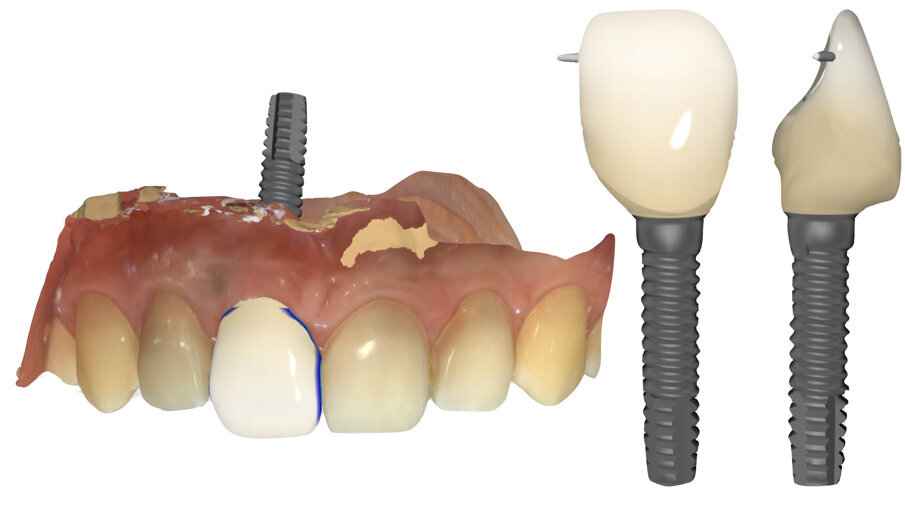

- Impronte digitali finali per la realizzazione del provvisorio immediato

Completata l’impronta, precedentemente sezionata, con la posizione tridimensionale dell’impianto inserito (Fig. 23), si procederà a disegnare il limite del profilo d’emergenza (Linea Base) sulla maschera gengivale (Fig. 24). Successivamente, selezionando la porzione anatomica del dente 2.1 (Linea di Copiatura) (Fig. 25), si creerà automaticamente, grazie al software di progettazione, il dente 1.1 (Fig. 26) che, una volta fresato in PMMA, verrà incollato alla base in titanio e, quindi, avvitato a 20 Ncm sull’impianto appena posizionato. Il reale vantaggio di questa tecnica consiste nel fatto che il provvisorio non dovrà essere ribasato con resina acrilica in bocca al paziente con il rischio di contaminare la matrice innestata. Il provvisorio, correttamente progettato grazie ad un profilo d’emergenza personalizzato, favorirà il condizionamento dei tessuti molli sostenendoli e, inoltre, sigillando il margine della ferita, proteggerà la matrice di collagene sottostante, garantendo, così, il risultato finale (Fig. 27).

In questa fase finale si è proceduto a finalizzare protesicamente il caso seguendo una metodica di lavoro digitale “chair-side”. La chiave di questo step è la funzione “Copia e Ribalta” che il software protesico mette a disposizione, mediante la quale è possibile copiare la morfologia del dente 2.1 al fine di realizzare il dente 1.1 con la medesima forma (Fig. 28).

- Elaborazione modelli master e progettazione digitale

Ultimata la fase d’impronta ci si affiderà al software per la progettazione dei denti definitivi. Per cominciare è necessario disegnare la “Linea Base” sul profilo dei tessuti molli, evidenziando l’area entro la quale il software rileverà e creerà una corona protesica con il corretto profilo d’emergenza in grado di sostenere le papille e la parabola gengivale precedentemente condizionate. Successivamente dovrà essere disegnata la “Linea di copiatura”, selezionando il dente la cui anatomia si vuole replicare. Il software, elaborate le informazioni inserite, creerà il dente protesico definitivo, specchiando l’anatomia dell’incisivo centrale vicino sull’impianto. Gli strumenti digitali che il software mette a disposizione costituiscono un valido ausilio per perfezionare la forma dei denti protesici (Fig. 32).